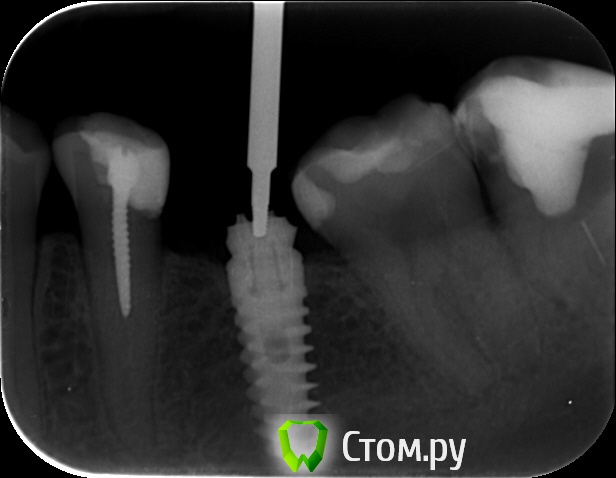

an_ver Опубликовано 29 мая, 2014 Поделиться Опубликовано 29 мая, 2014 Кто то пытался достать))) Абатмент спили в ноль...головку винта своротили.Набор Нео 3 Ссылка на комментарий

an_ver Опубликовано 29 мая, 2014 Автор Поделиться Опубликовано 29 мая, 2014 Теперь когда что то будет где то застревать , я знаю к кому обращаться))Молодец!!Обычно УЗ доставал а тут решил набор обновить))) Ссылка на комментарий

Magomed Опубликовано 2 июня, 2014 Поделиться Опубликовано 2 июня, 2014 резорцин всех спасает и даже анкер на 45 Ссылка на комментарий